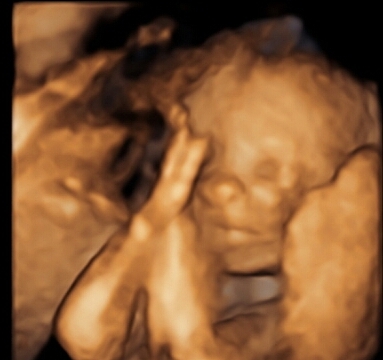

Sorry if giant. 3D ultrasounds are a bit weird but it was so cool to see his face. He has my lips for sure and his daddy's nose. Taken at 25w3d

she looks so content, almost like she's smiling